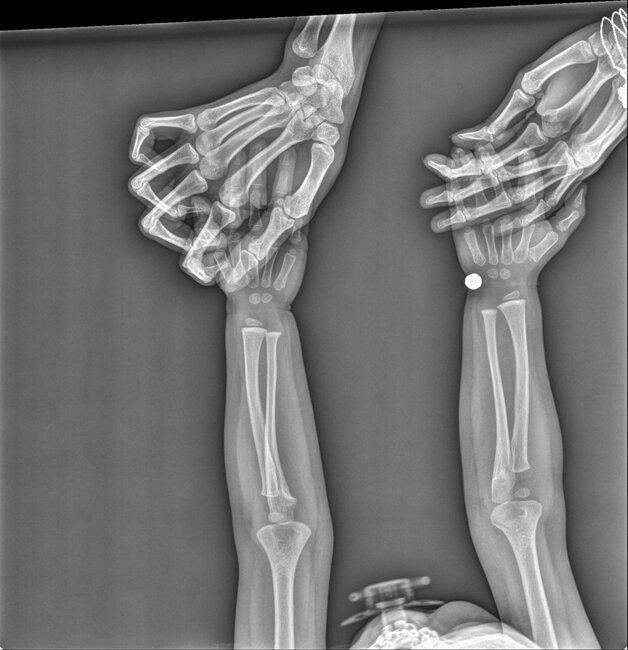

Azərbaycanda həkim azyaşlı uşağa səhv diaqnoz qoyub. Jurnalist Aytən Sakitqızı -a açıqlamasında bildirib ki, hadisə "Baku Medical Plaza"da qeydə alınıb. Onun sözlərinə görə, adıçəkilən klinikanın travmatoloqu Şamama Cəfərova onun 1 yaşlı qızına yalandan qolunun sınığı diaqnozunu qoyub:. "Qızı